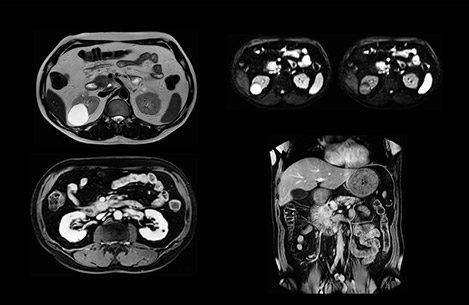

In this example the image quality of the MultiVane XD images is evidently better than in the images without MultiVane XD. Ingenia 1.5T with dS Torso coil solution.

“Our liver exams are quite fast,” says Dr. Baumann. “If the patient tolerates it, we use an arms-up position to reduce the FOV and speed up the exam with dS SENSE.” “We acquire one transversal high resolution T2-weighted sequence with 3 mm slice thickness, for example for pancreas or liver lesions. Then we also add a T2 fat suppressed MultiVane XD SPIR sequence. We perform these two routinely in our liver imaging. We use high dS SENSE factors to significantly shorten scan times to 2-4 minutes, which can improve our protocol; it’s a very robust scan.” “We include mDIXON for the dynamic sequences because of the robust and homogeneous fat suppression we get with that. We had been using eTHRIVE, but we are now quite happy with mDIXON. Sometimes we use a medication to calm the bowels, to further improve the image quality.”